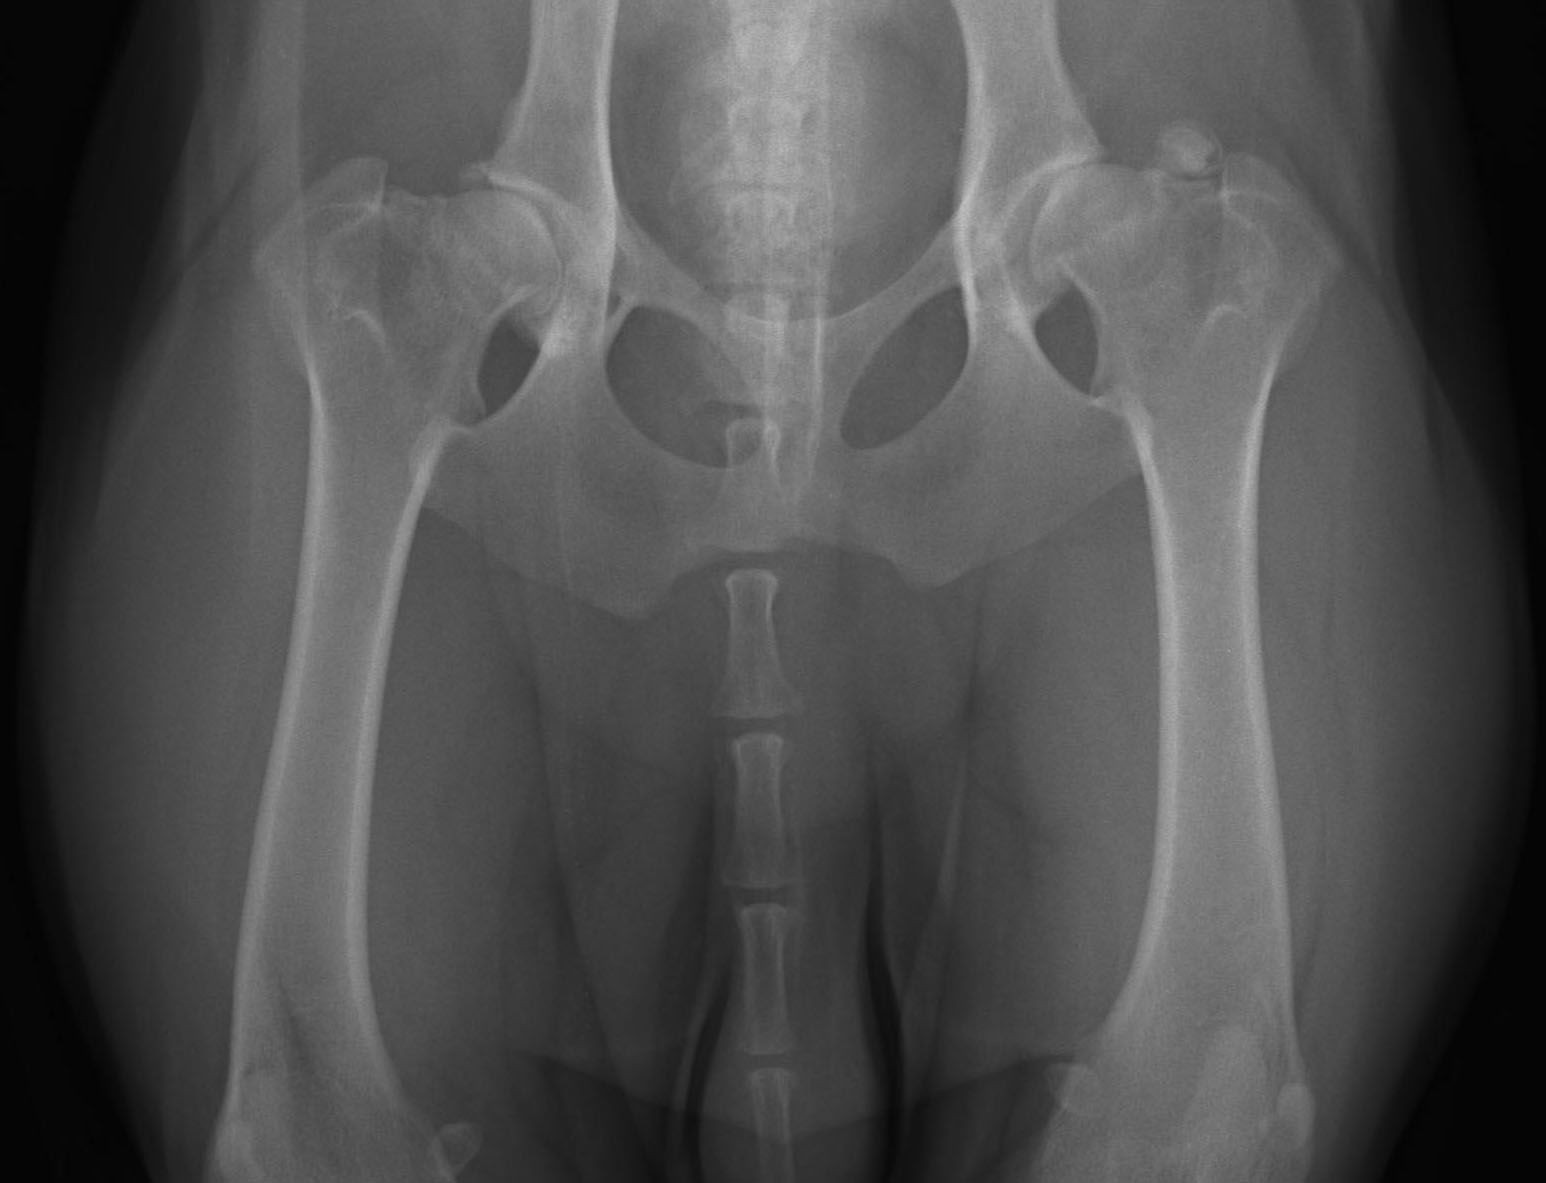

Heupdysplasie (HD)

Heupdysplasie (HD) is een ontwikkelingsstoornis van de heupgewrichten. Het kan erfelijk zijn, maar omgevingsfactoren spelen ook een rol bij de ontwikkeling. Een hond kan veel last hebben van HD, maar dat hoeft niet. Aan de buitenkant kun je niet zien of een hond HD heeft, dus als je hond goed kan lopen, hoeft dat nog niet te zeggen dat zijn heupen perfect zijn. Om echt te kunnen zien of je hond HD heeft, zijn (digitale) röntgenfoto’s van zijn heupen nodig.